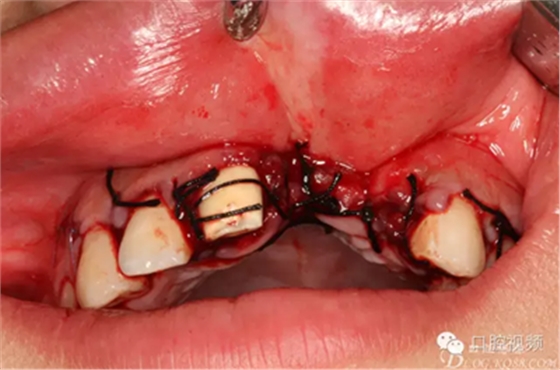

圖8.切開、翻瓣、完整暴露壞死部分牙槽骨

圖9.牙槽骨壞死達鼻底

圖14.直接縫合關(guān)閉創(chuàng)面。